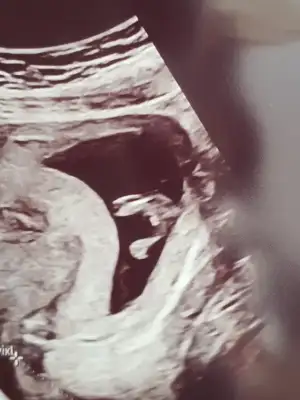

Bacak arasi dolu gibi ya herkes erkek dedi o yüzden. Bacak arası böyle olup yine kız olabiliyor muuKız görünüyor

Omu doluBacak arasi dolu gibi ya herkes erkek dedi o yüzden. Bacak arası böyle olup yine kız olabiliyor muu

Bu gercekten daha doluOmu doluo dolu ise bu nedir 13 haftaEki Görüntüle 2826253